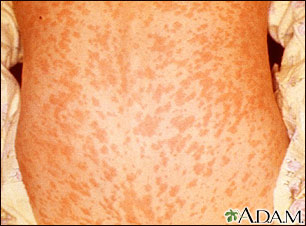

Side Effects of MMR and MMRV Vaccines

Common side effects include:

- Fever

- Rash and itching

- Mild swelling of the salivary glands

- Joint pain